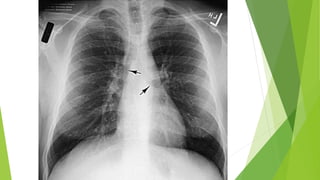

Signo del Broncograma Aéreo:

 La silueta cardíaca a menudo

oculta la patología del

lóbulo inferior izquierdo en

las radiografías AP y PA

 El signo del broncograma

aéreo superpuesto a la

silueta cardíaca es el signo

definitivo de consolidación

en el lóbulo inferior

izquierdo

Signo del BroncogramaAéreo:  La silueta cardíaca a menudo oculta la patología del lóbulo inferior izquierdo en las radiografías AP y PA  El signo del broncograma aéreo superpuesto a la silueta cardíaca es el signo definitivo de consolidación en el lóbulo inferior izquierdo